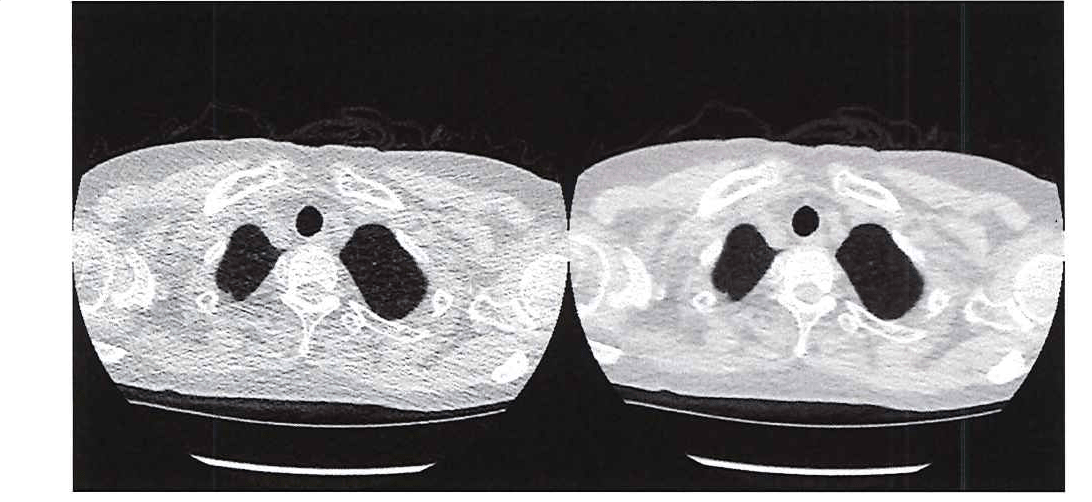

Medical researchers want to limit radiation exposure while providing physicians with the image clarity they need. One promising approach is the use of ultra-low-dose CT, which has an effective average dose of about 0.13 mSv for a chest image. [1] The principal drawback of ultra-low-dose CT scans is their relatively low resolution and high level of noise, which can make it difficult for physicians to see organs, fat, and interstitial tissue (Figure 1).

Figure 1. Comparing the image quality of ultra-low-dose CT (left) with a traditional CT (right).